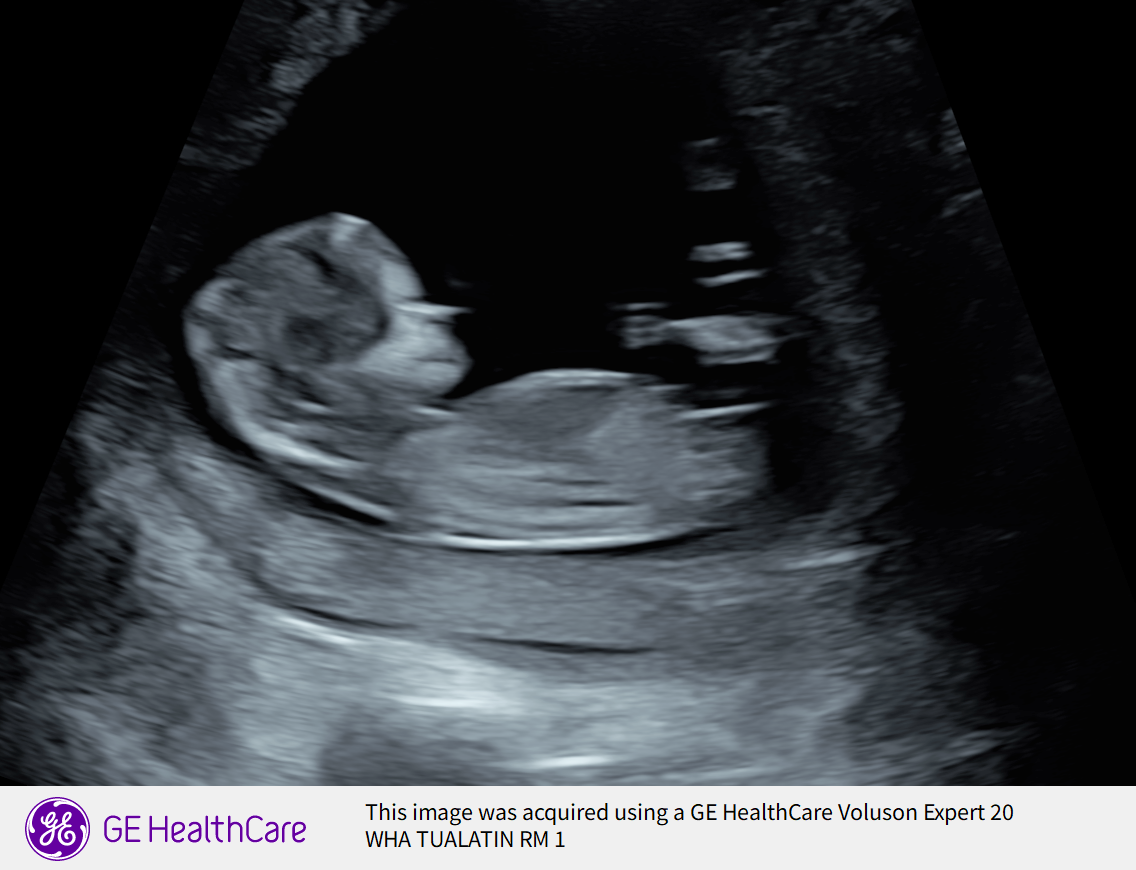

On January 16th, we went to our “routine” anatomy scan-—that quickly became the most terrifying day of our lives.

After our scan the doctor came in and told us there was something on the scan she needed to discuss with us. We learned quickly that our son was diagnosed with CDH (Congenital Diaphragmatic Hernia). We learned that he has a hole in his diaphragm and his heart is on the wrong side, his left lung is compromised and unfortunately this has made it so his little lungs can’t develop to the size they need to be. After hearing this information we were told how severe this diagnosis is and that we needed to look at survival rates. We knew we would need to deliver at a high risk unit and due to severity we would be needing to relocate to a hospital that specializes in CDH surgery, NICU care.